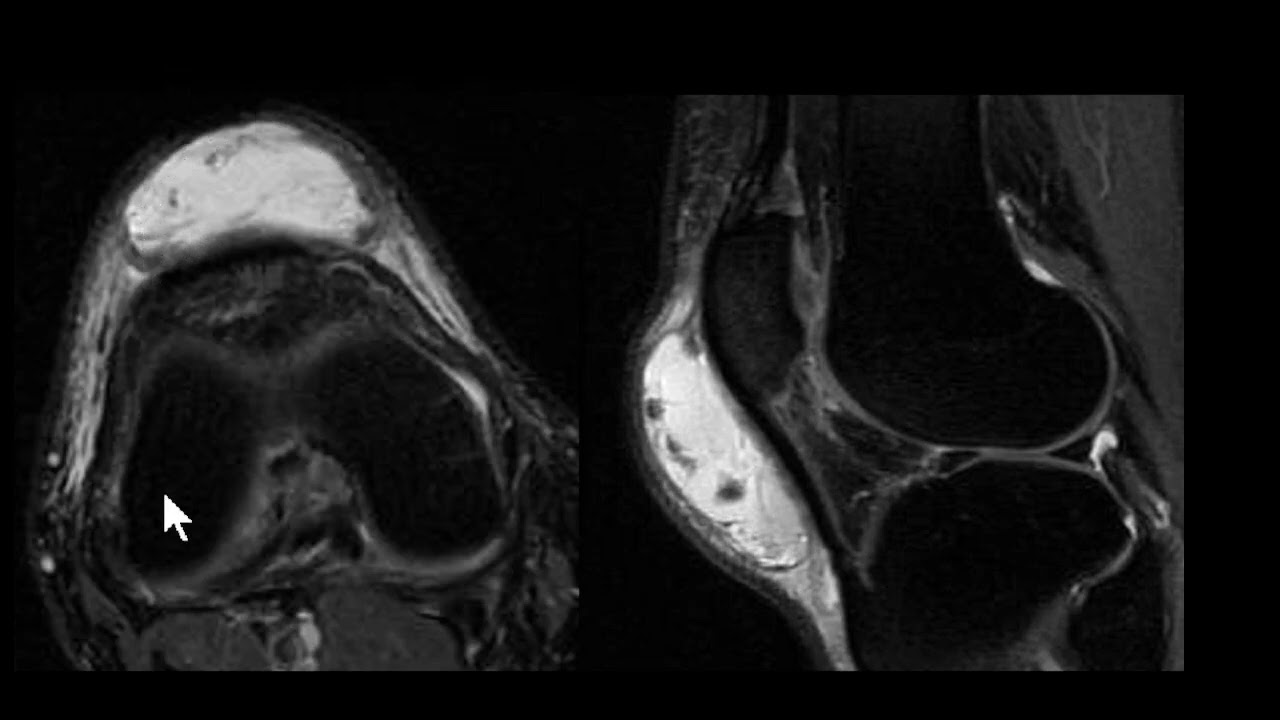

saudações vamos aqui a Mais Um Caso o contexto clínico é de um paciente que sofreu uma torção aguda do tornozelo e temos essa ressonância magnética aqui um axial DP com saturação de gordura e vamos observar aqui aqui é a fíbula corte aqui no plano axial aqui a fíbula aqui o talos aqui a tíbia né então o ligamento tíbio talar anter inferior está íntegro vamos descendo aqui aqui é a topografia do ligamento talofibular anterior aqui o ligamento talofibular posterior e você observa aqui no ligamento talo fibular anterior veja que ele está espessado está com hipersinal e

você nota nitidamente uma solução de continuidade né uma ruptura aí do ligamento talofibular anterior e edema ao seu redor existem outras alterações mas a gente vai se ater a essa alteração o ligamento talofibular posterior ele tem esse aspecto radiado né rajado é normal e o ligamento calcâneo fibular esse aqui na ponta da seta está íntegro apesar de haver edema ao redor dele então o ligamento talo fibular anterior rompeu e essa é a rotura mais frequente ligamentar no tornozelo do ligamento talofibular anterior aqui pra gente ver um comparativo com um tornozelo normal você Observe aqui a

fíbula aqui o talos e aqui você vê o ligamento talo fibular anterior aqui é uma sequência T1 e aqui uma sequência T2 com saturação de gordura você veja aí o ligamento talofibular anterior veja como ele é né em condições normais aí o ligamento talofibular anterior aqui o talo fibular posterior n talo fibular posterior ele tem esse aspecto rajado e descendo um pouco mais o calcâneo fibular fininho aqui subindo calcando fibular saio daqui e vem para cá mas o importante aqui É vermos o ligamento talo fibular anterior normal o aspecto normal dele ok Neste vídeo era